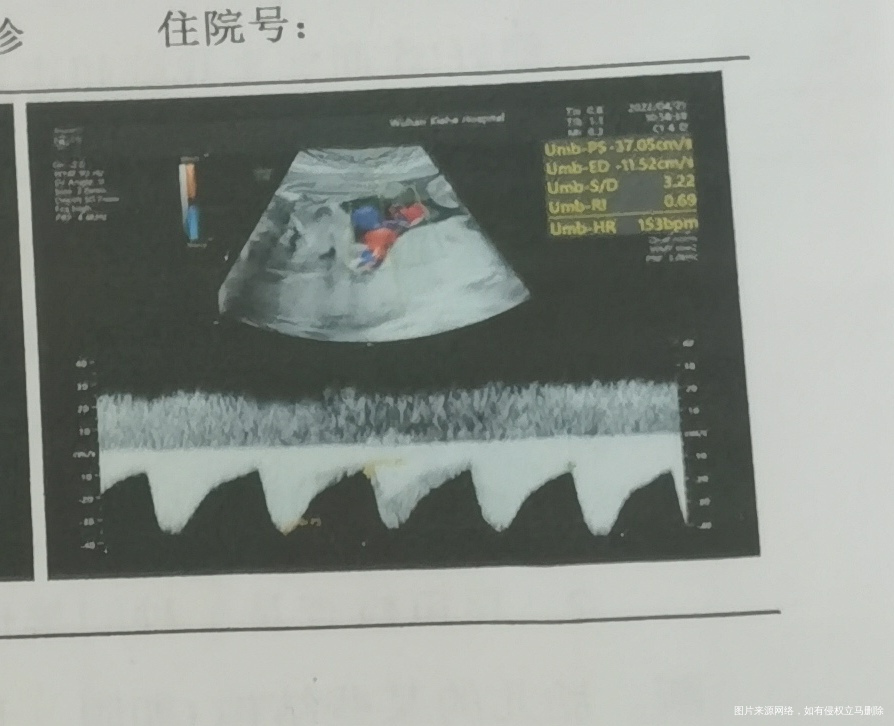

这个图是心脏吗?下面的是心脏波动吗?我看别人的上面波动没有这么大,我这个会不会不好。

图像看不出是心脏,但波行相识心脏跳动的波形频谱,,只要胎心好就行,不必纠结,每个胎儿不一样,怀孕孕周不一样,彩超机器也不一样,图像放大程度也不一样的,祝你好孕。

你这测的是胎儿的血流图,胎心率153次/分,正常服务,S/D比值3.22,如果是30周前正常,30周后大于3就高了,表示有脐血管阻力高缺氧可能,还要结合其它指标判断,下次发整个B超报告看。

你好,这个是脐血流,你的数值3.22,随着孕周增加数值减低。

这个应该测的是脐带的血流,主要是看收缩期,舒张期血流频谱,计算S/D值。咱们重点应该关注的是S/D值,再结合孕周考虑,孕39周正常小于3。